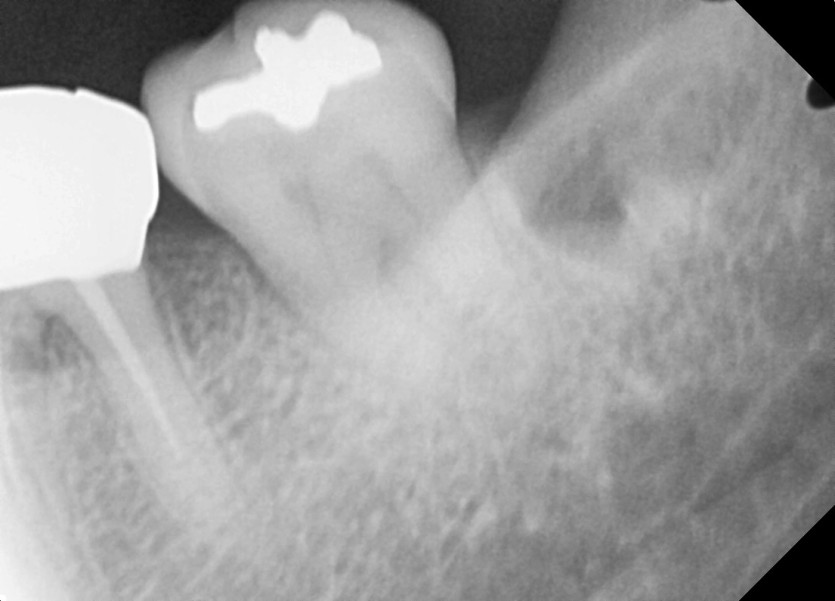

#38 사랑니 발치

구강 외과 전문의가 당일 발치했습니다.